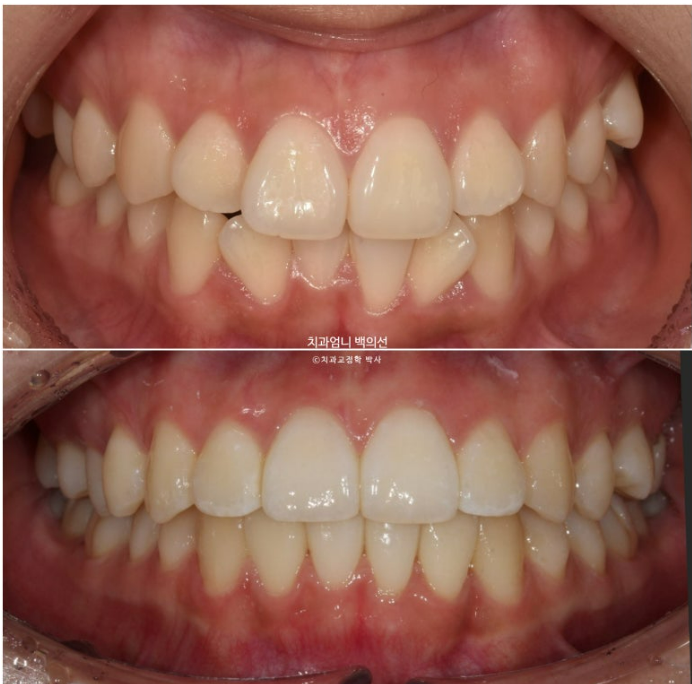

이제 전 후 비교해보겠습니다.

23.12~24.09

고무줄 사용으로 송곳니 교합관계도 개선되었습니다.

주변치아에 비해 유난히 커보였던 앞니는 높낮이와 배열이 맞아지니 이제는 커보이지 않습니다.

치간삭제를 동반하여 앞니를 배열했기 때문에 처음에 비해 돌출되지 않고 유지되었고 원래 예뻤던 입매도 잘 유지가 되었습니다.